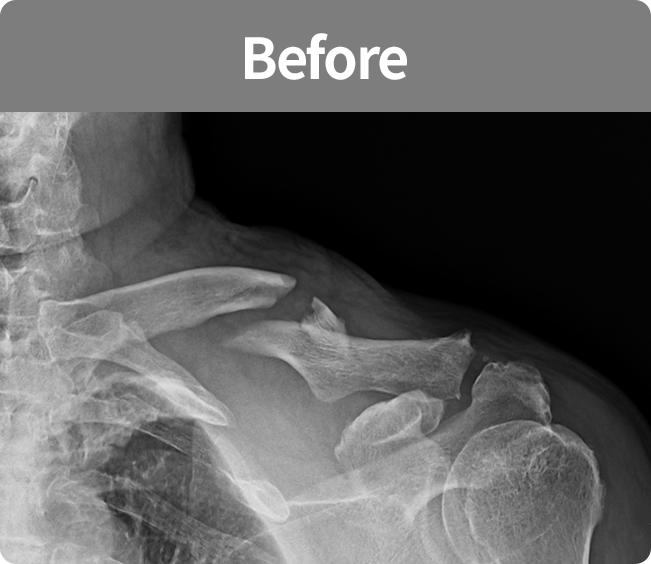

골절 고정술

부러진 뼈를 해부학적 위치로 정확하게 맞춘 뒤,

뼈가 안정적으로 붙을 수 있도록

금속판, 나사, 핀 등을 이용해

고정하는 수술(내고정술, 외고정술)

뼈가 안정적으로 붙을 수 있도록 금속판, 나사, 핀 등을 이용해 고정하는 수술

(내고정술, 외고정술)